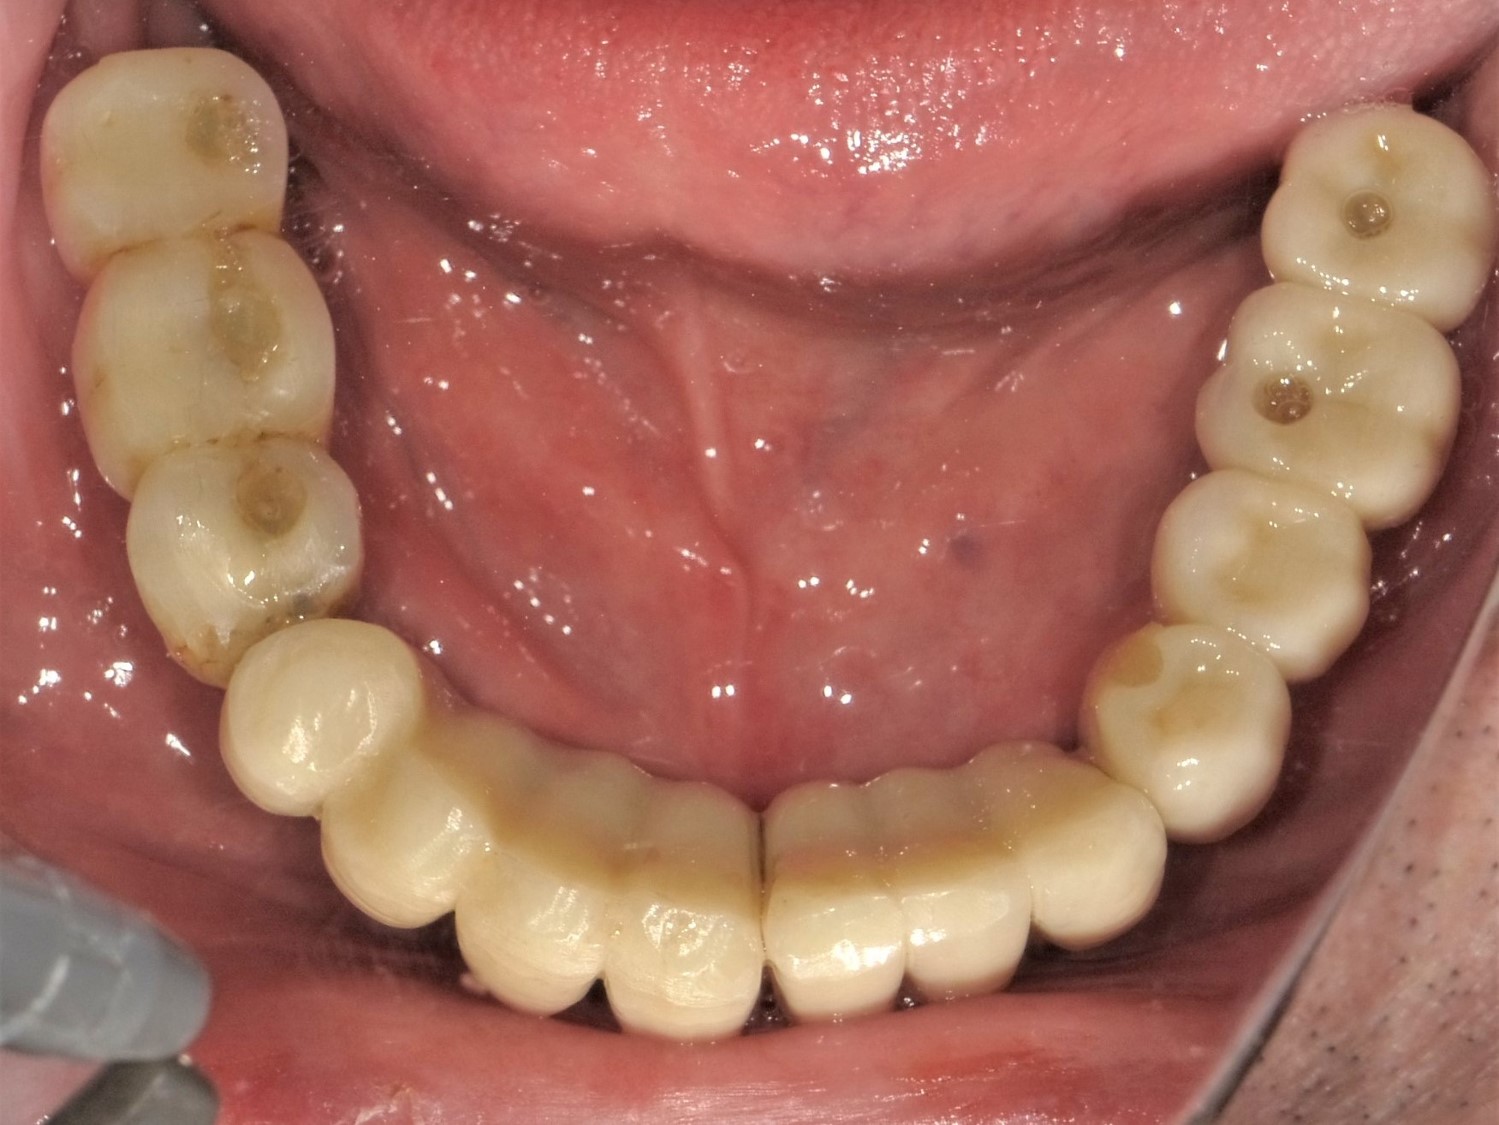

- 下顎の無歯顎ケース

下顎前歯ならびに左側臼歯部にインプラント補綴を他院で受けていたが次々にインプラントが抜け落ち、治療は無理といわれて義歯を入れている。残った2本の自分の歯もぐらぐらしてきて、入れ歯で食事ができなくなってしまったということで、どうにかもう一度インプラント治療できないかと当クリニックを受診されました。

右側臼歯部のインプラント補綴も、インプラント体の周囲が吸収していますが、どうにか動揺して脱落するまでは使いたいとのことで温存することにしました。

右側の第1,第2小臼歯(#41,42)は歯周病と根尖性歯周病で動揺しており、保存不可とお話ししました。

最終補綴物装着時の口腔内所見